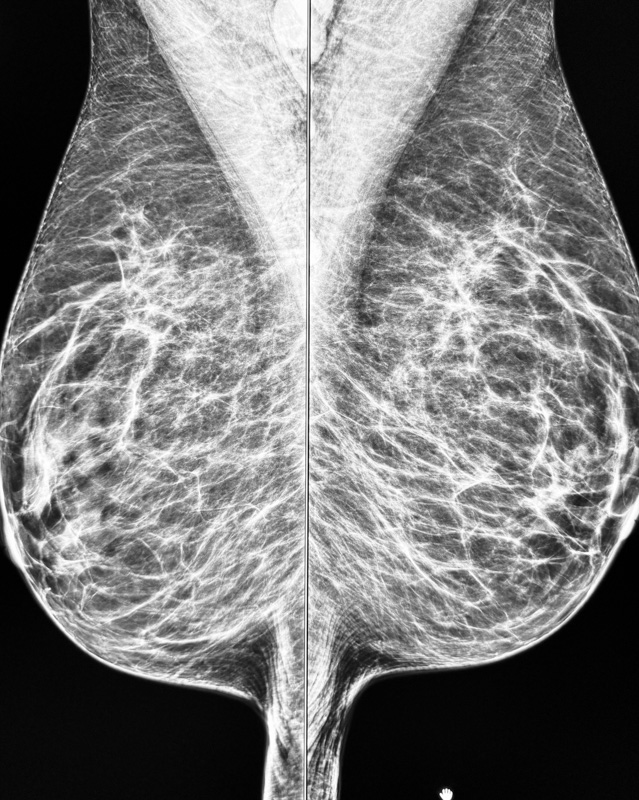

Mammographie / Tomosynthese

Die Mammographie ist die Röntgenaufnahme speziell für die Brust. Bei dieser Untersuchung zur Früherkennung und Diagnose von Brustkrebs setzen wir hochmoderne, digitale Geräte ein. Dabei machen unsere Mammographiebilder bereits kleinste Kalkablagerungen sichtbar und bieten damit wertvolle Anhaltspunkte für eine frühzeitige Therapie.

Die Tomosynthese:

Die Tomosynthese ist ein spezielles Röntgenverfahren der Brust. Hierbei wird die Brust in einzelnen Schichten, ähnlich einer CT-Untersuchung dargestellt. Dadurch können kleinere Tumore insbesondere bei dichten Drüsenkörpern besser und eher dargestellt werden. Die Tomosynthese bedeutet also mehr Sicherheit für Sie als Patientin.